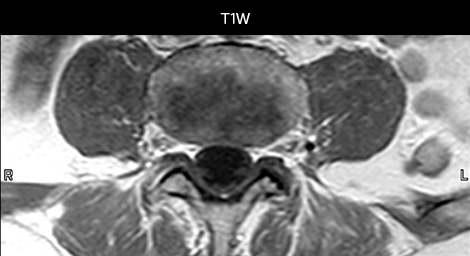

Including mDIXON TSE for robust fat suppression

“We use mDIXON TSE extensively in our spine imaging in the emergency room,” says Dr. Karis. “It’s particularly nice in that it is very robust with regard to susceptibility type of problems that would come up with traditional spectral fat-saturated images; these problems are essentially eliminated with the mDIXON technique. In our ED environment it’s really nice to have the fat-free imaging that goes along with the mDIXON technique.

“For the thoracic and cervical spine routine non-contrast exam, for example, we perform one mDIXON T2 TSE sequence, which provides us with two outputs: the fat-and-water-together T2-weighted images, as well as the water-only sagittal T2-weighted images. And then we also perform an axial gradient echo exam.”